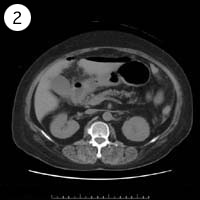

57歳 女性

異常のある4枚組は?

単純CT